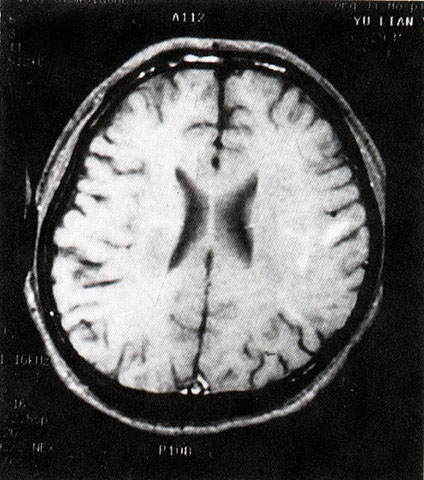

FH1046 脑炎性感染(MRI)

光盘检索编码 FH1046 函授作业图编号 1046

图 名 脑炎性感染

导 学 阅图分析

讨 论 题 阅图分析